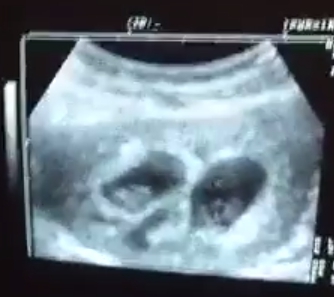

做精子銀行試管嬰兒雙胞胎大出血,血照流,雙胞胎兒照樣長大

雙胞胎一直流血 胎兒照長大